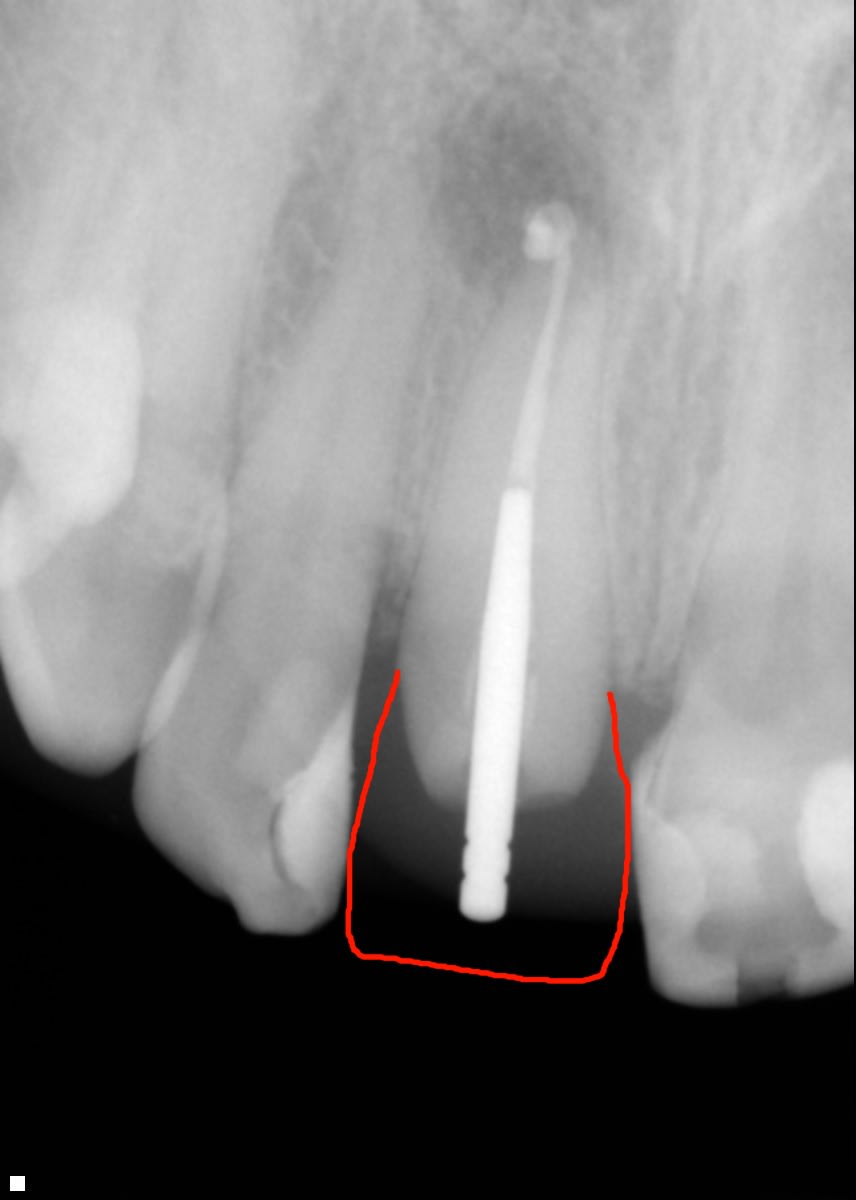

voici la radio

Gencive moche et méga pêche apicale... si je peux me permettre..; je ferai une vraie prépa plutôt juxta gingivale/une provisoire bien adaptée en légère sous-occ /je scelle au Durelon en éliminant bien les excès... et je laisse dormir tout l'été... A la rentrée rx et couronne si tout est ok !!...

probablement espace bio pas bon (cf photo que jai mis où je pense deviner la position du congé)

Pour moi a la radio t'es trop sous gingival

Soit tu attends que l'inflamation cesse (ca va prendre 2 mois au moins) et l'espace bio va se recreer tout seul avec la fonte osseuse

Soit tu fais une elongation coronaire

008 isy1j2 kxansn - Eugenol